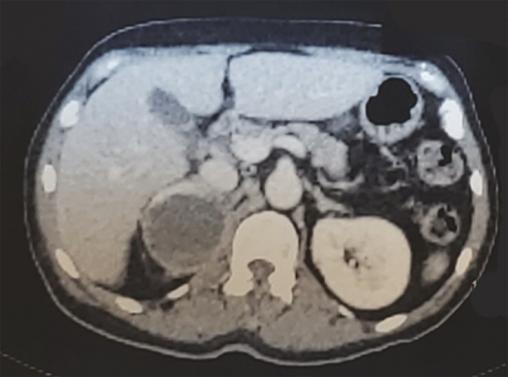

La biopsie de la tumeur a révélé une prolifération maligne dermique, composée de cellules rondes d’aspect épithélioïde, de grande taille et pourvues de volumineux noyaux ovoïdes hyperchromatiques et anisocaryotiques, positive pour Melan-A, PS100 et HMB-45 en immunohistochimie. La biopsie-exérèse d’un nodule sous-cutané dorsal était en faveur d’une métastase. Le diagnostic de sarcome cutané à cellules claires (SCC) a été retenu, et le bilan d’extension a objectivé une masse surrénalienne droite (fig. 2) : un phéochromocytome a été évoqué, puis confirmé par un taux élevé de catécholamines et de leurs dérivés méthoxylés. La patiente a bénéficié de l’exérèse chirurgicale de la masse surrénalienne et de la tumeur cutanée, puis a été adressée en oncologie pour une chimiothérapie.